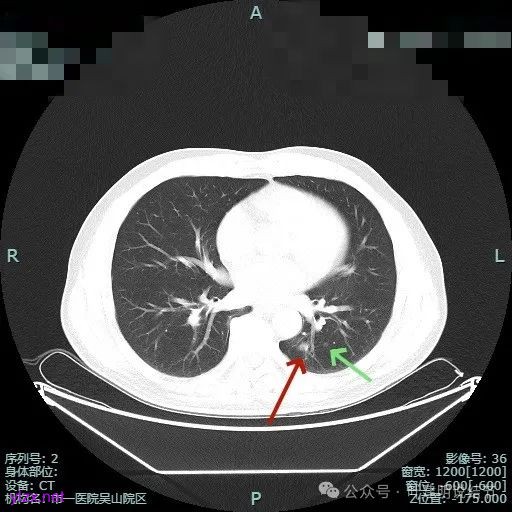

主病灶位于下叶后基底段下肺静脉水平,次病灶在同一层面位靠外基底段交界附近。

薄层上看主病灶不纯,有实性成分,也有血管穿行;次病灶是纯磨,微小的结节,但轮廓与边界较为清楚。

主病灶混合密度,血管进入;次病灶小且淡,但轮廓清。